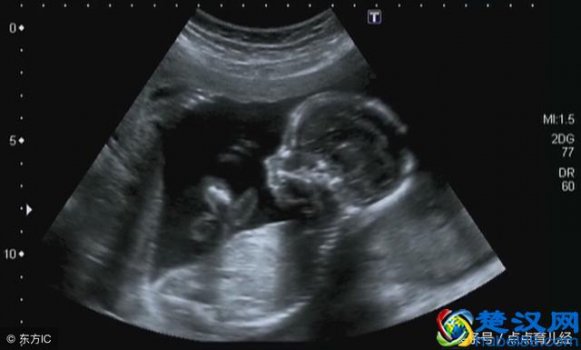

三维彩超检查哪些项目(三维彩超几周做合适)

孕期B超、彩超检查大家并不陌生,只是各种超种类真多,让人摸不清头脑,到底B超、彩超、三维、四维是什么东西,它们有什么区别吗?孕检期间常规的必须要做的超声检查是哪一个? 首先来说一说这几种超声检查: 1、 B超 是最普通的检查,它的成像是黑白的、絮状的,就像.....[详细]